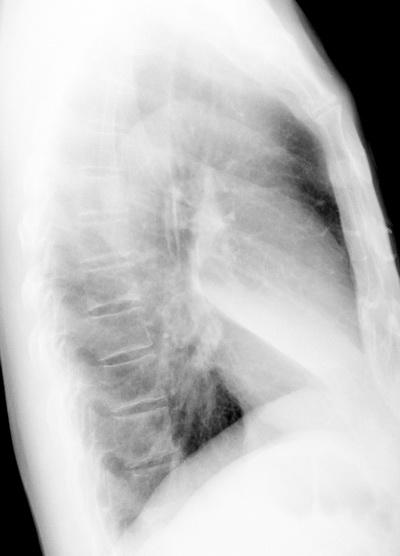

考虑右肺中叶不张,请大家发表意见

右肺中叶不张、肺门轮廓增大,占位不除外;建议增强,必要时支气管镜详查。

右肺中叶不张,中叶支气管开口不清,建议支气管镜检查。

右肺中叶支气管闭塞,中叶肺不张,右侧肺门见肿块影。中心型肺癌的可能大。建议支气管镜检查。

右中叶体积明显缩小,且其支气管未显示,先考虑:中心型肺癌班右中叶肺不张。

建议:支气管镜检查。

平片就可以诊断右肺中叶不张,做CT就是要找原因!中叶支气管开口不清,建议支气管镜检查。